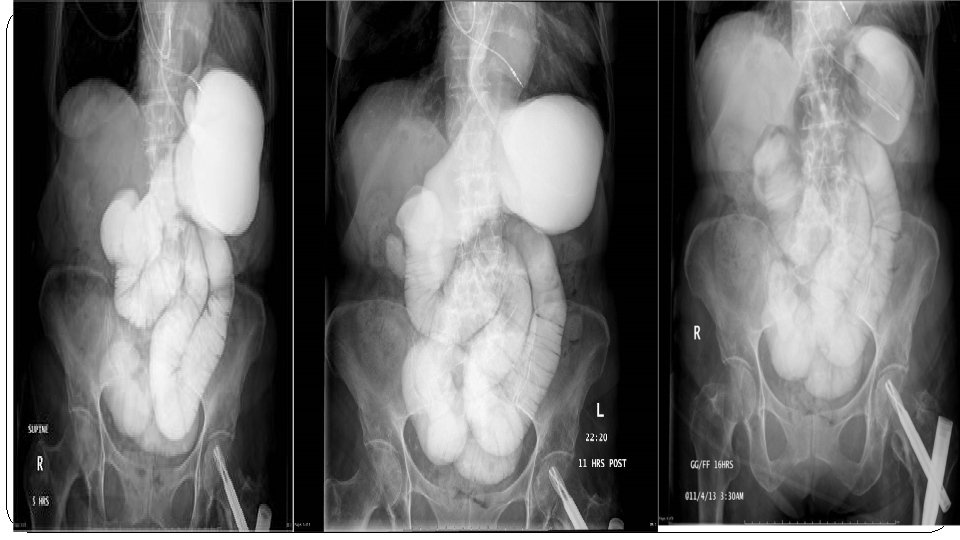

Findings on imaging. . . � 1 -Dilated bowel loops proximal to obstruction. � 2 -Collapsed bowel loops distal to obstruction � 3 -No air within rectum � 4 -Multiple air-fluid levels � 5 -Cause of obstruction (e. g. , tumor)

Diagnosis. . . �In the workup of suspected mechanical bowel obstruction, imaging allows for quick confirmation of the diagnosis as well as detection of conditions requring immediate surgery (e. g. , perforation). � Small bowel dilatation if > 3 cm �n SBO: The dilated loops are predominantly central

PARALYTIC ILEUS SECONDARY TO MESENTRIC ISCHEMIA • Abdominal X-ray AP view : 1 - multiple dilated loop of bowel 2 - several air fluid level

• Abdominal X-ray left lateral view : Significantly distended intestinal loops with air fluid levels are visible

• The fluid levels long and at the same level. • Gases in both colon and small bowel loops.